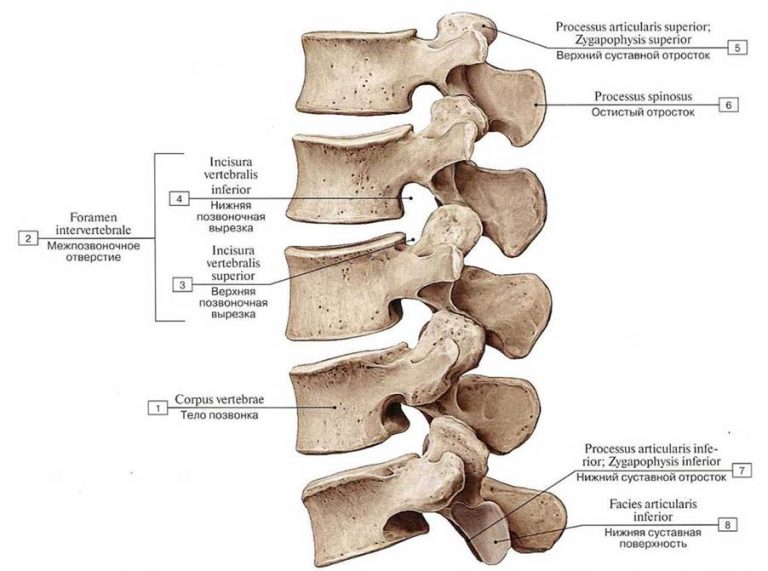

Структура позвоночника: сегменты и тазовые отделы в фотографиях